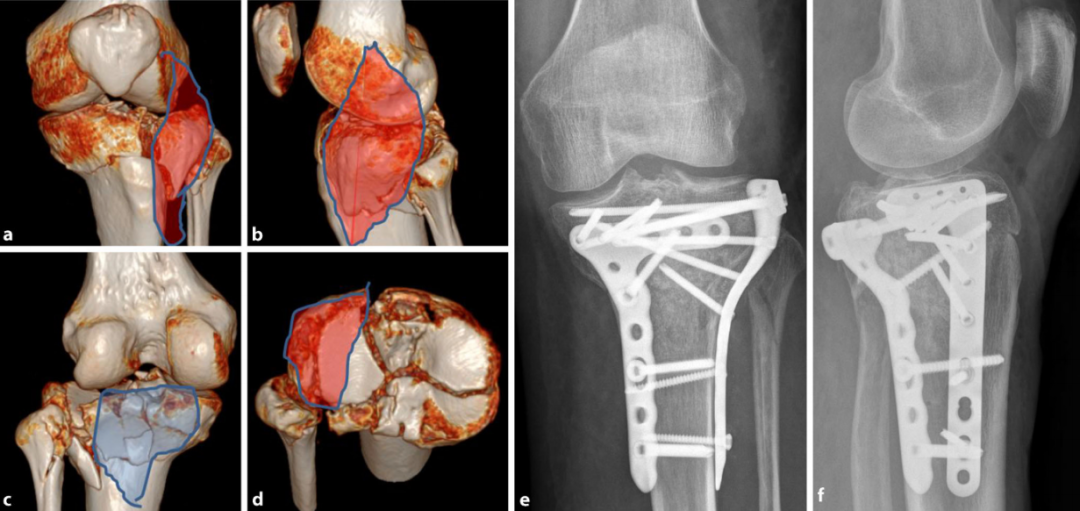

图15:a–d 术前计划CT(计算机断层扫描):外翻/伸展型骨折累及内侧柱、外侧柱及后柱。

-

仰卧位后内侧入路(蓝色)固定内侧柱。本例后柱为简单骨折,无需后侧支撑。

扩展前外侧入路(红色)显露外侧柱及胫骨平台外侧,固定胫骨结节骨折块并行平台支撑(Rafting技术)。

e, f 术后首次体位验证。g, h 术后10周随访影像。